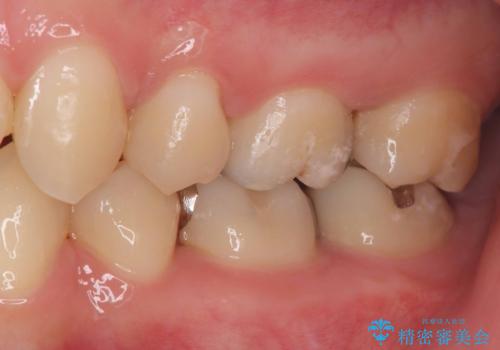

- 虫歯が神経まで達していたのですが、術前の検査と顕微鏡下で見た神経の状態からVPTの適応と判断し神経を残す治療をしました。

矯正治療も当院で行ったので、矯正治療終了後オールセラミッククラウンで治療を行いました。

汚染されている神経は除去し残りの神経を残すためVPTを行いバイオセラミックのバイオシーシーラーで充填しオールセラミッククラウンで治療を行いました。治療後2年経過しましたが、神経は温存され経過は良好です。